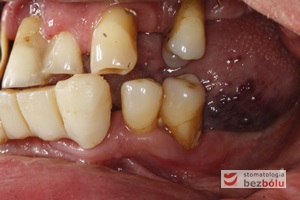

Stan wyjściowy - patologiczne wychylenie zębów górnych, liczne braki zębowe w szczęce i żuchwie, nieproporcjonalnie małe zęby do podstaw kostnych

Stan wyjściowy – patologiczne wychylenie zębów górnych, liczne braki zębowe w szczęce i żuchwie, nieproporcjonalnie małe zęby do podstaw kostnych

Braki zębowe w strefach bocznych szczęki i żuchwy - widoczne starcie patologiczne na skutek przeciążeń okluzyjnych w odcinku przednim

Braki zębowe w strefach bocznych szczęki i żuchwy – widoczne starcie patologiczne na skutek przeciążeń okluzyjnych w odcinku przednim